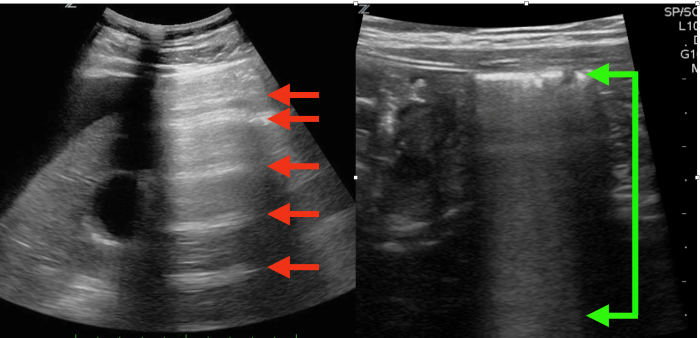

Bowel ultrasound showing a large amount of intraluminal fluid representing ongoing losses from diarrhea.

A flat, slit-like IVC is seen with little respiratory variation.

The left image red arrows shows reverberating horizontal A lines in the abdomen indicating free air from a ruptured viscus, the right image green arrows shows how normal bowel gas appears.